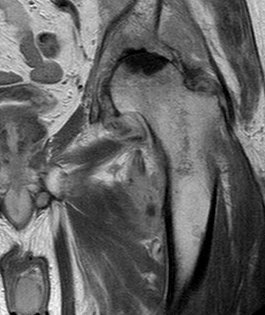

MRI is very sensitive but may still struggle to differentiate between advanced sepsis and AVN.